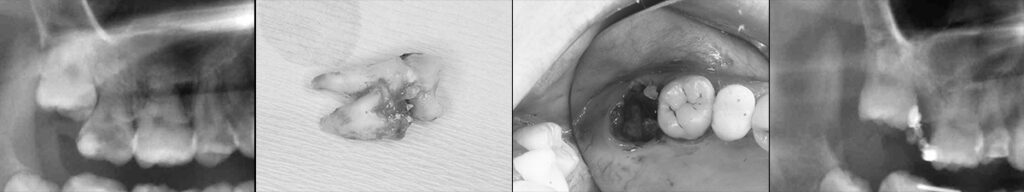

参考) 腐食した上顎第二大臼歯部に後方埋伏智歯を挺出矯正させ置き換えた例1

参考) 腐食した上顎第二大臼歯部に後方埋伏智歯を挺出矯正させ置き換えた例2